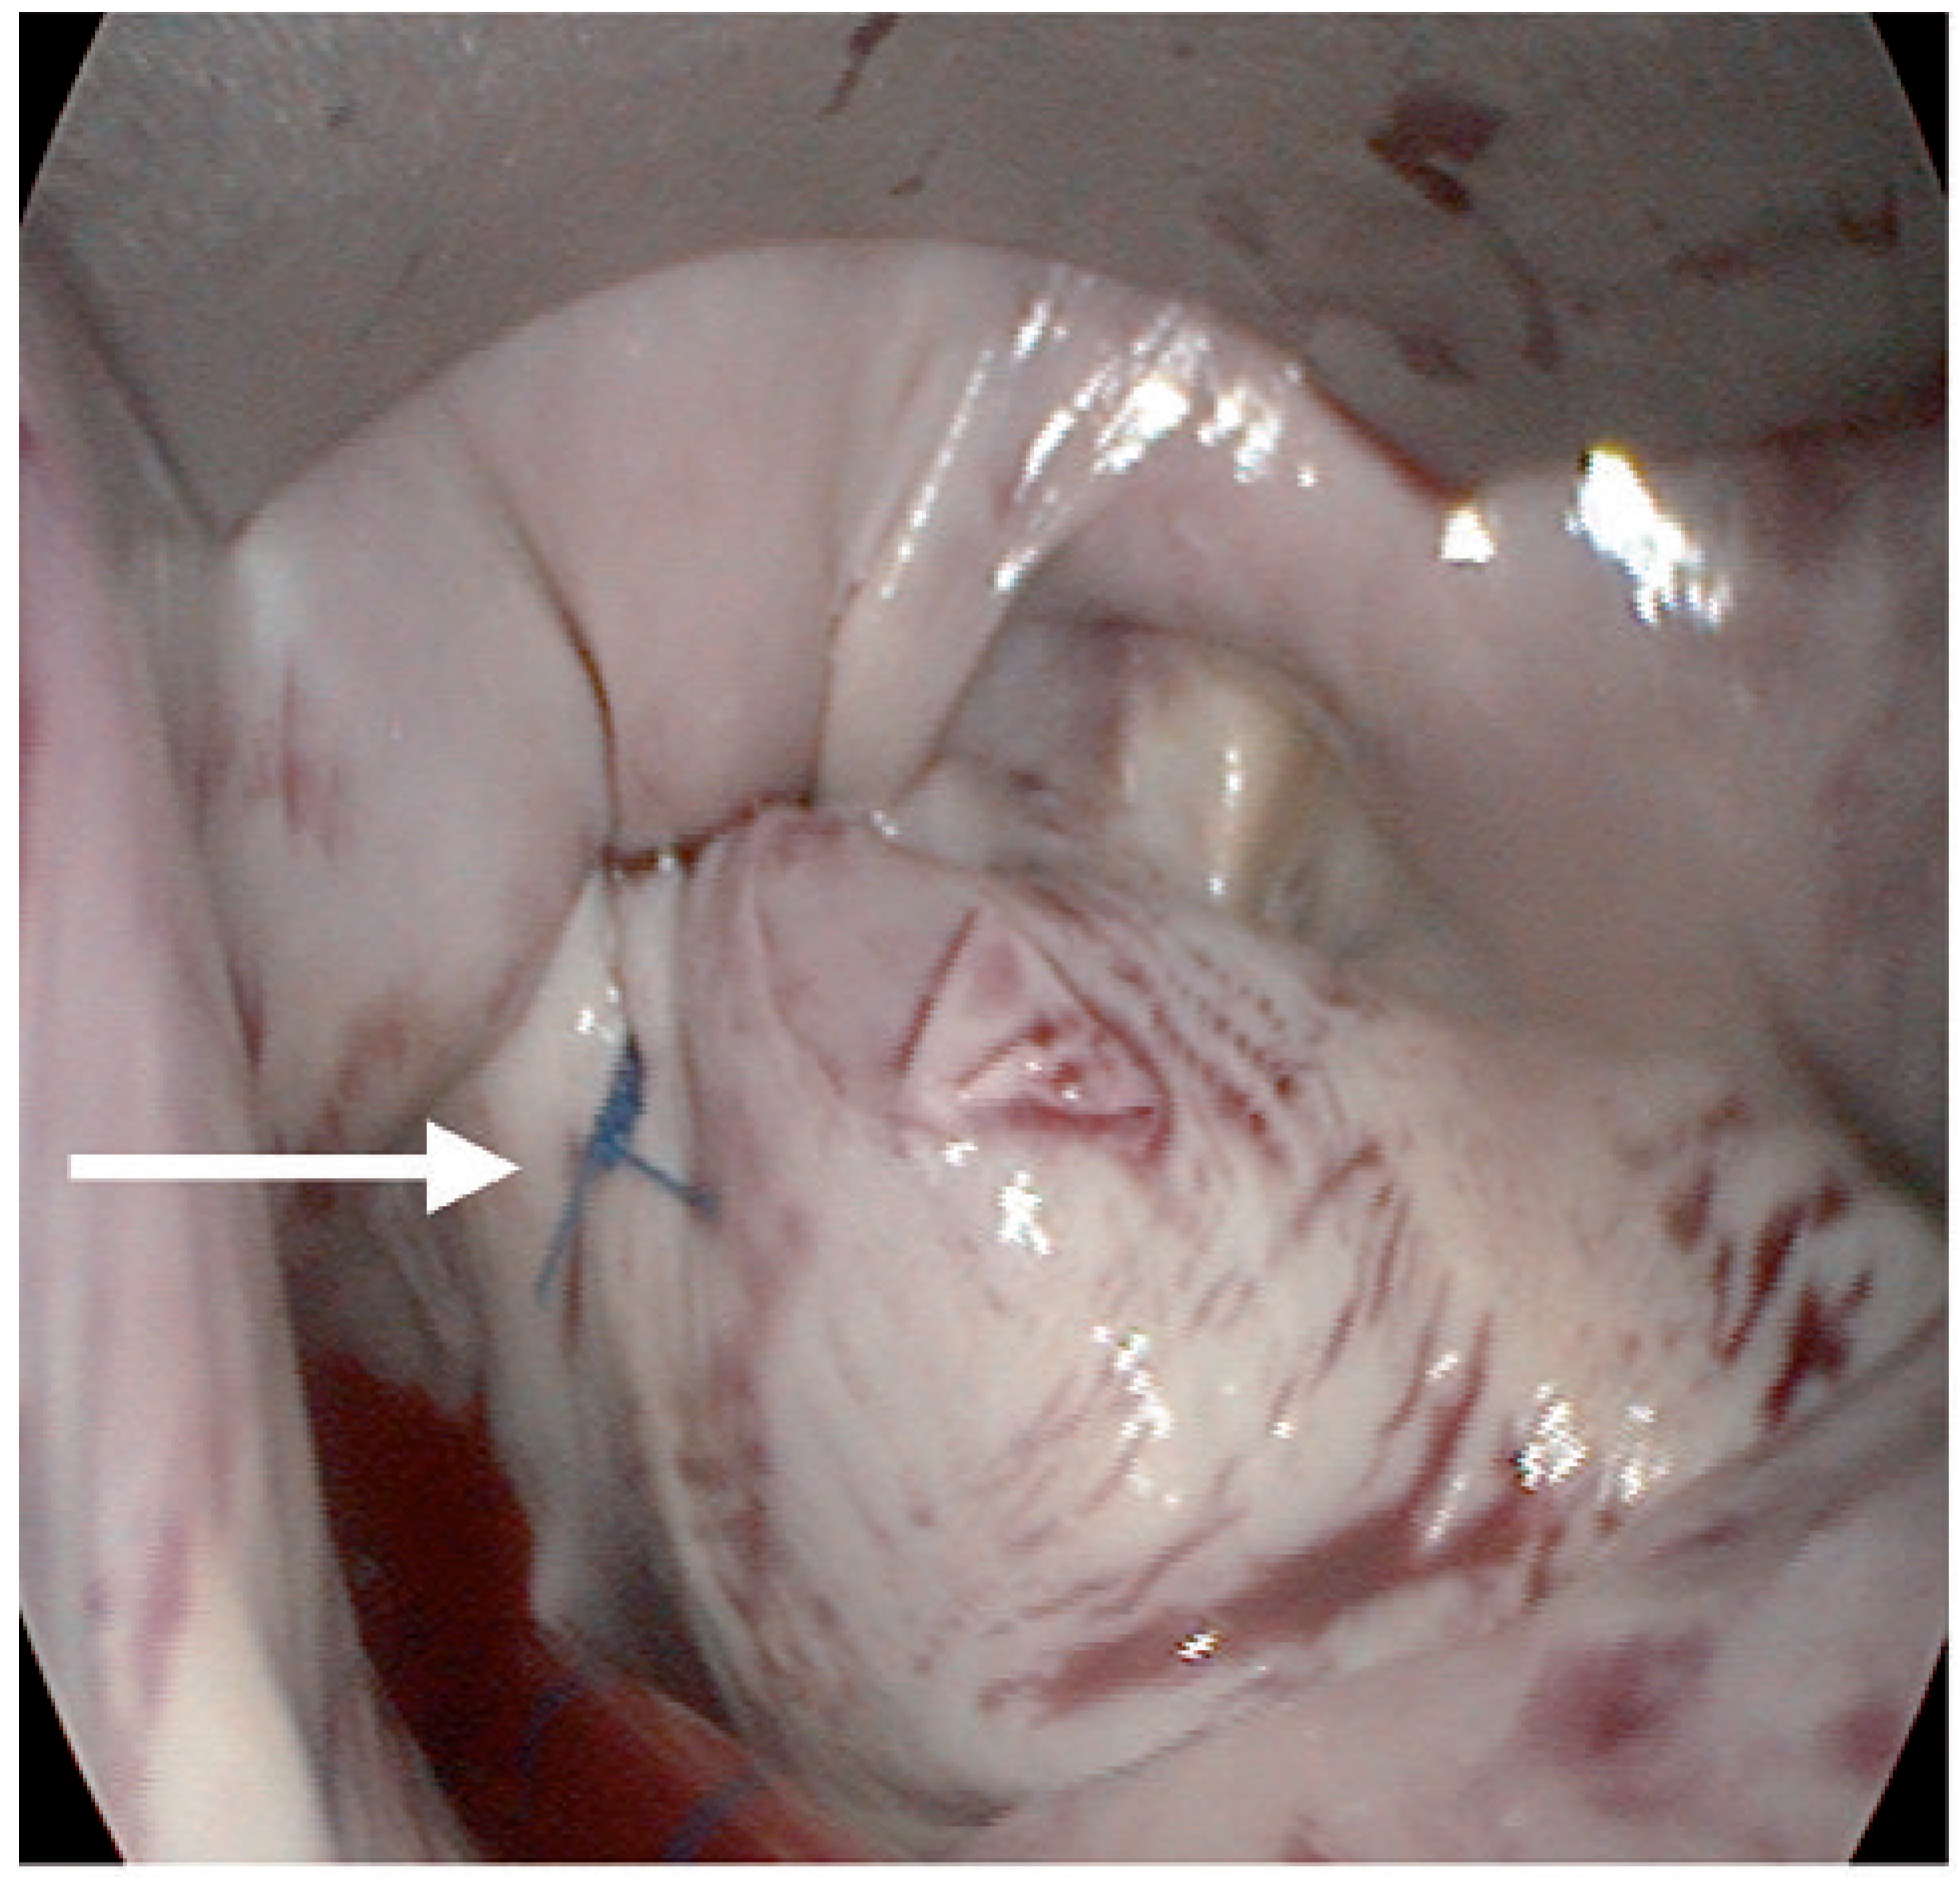

Fallbeschreibung